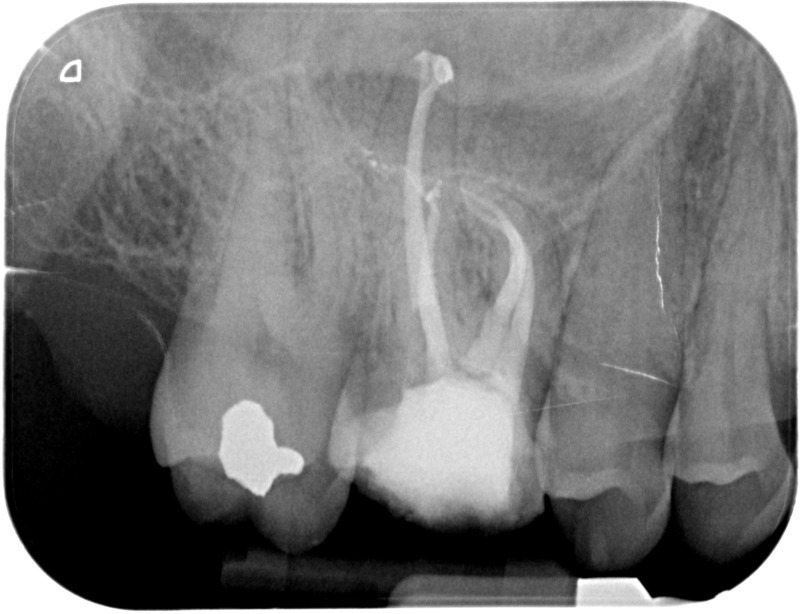

Avant

• Reprise de traitement endodontique : La manœuvre consiste à retourner à l’intérieur des racines d’une dent déjà traitée. Il arrive occasionnellement qu’une nouvelle inflammation se déclare suite à une reprise de carie ou une fracture de la dent, ou si le premier traitement endodontique est incomplet. Après s’être assuré que la dent lésée était conservable, il convient de désinfecter de nouveau le réseau canalaire parfois très complexe. La nouvelle obturation des canaux devra être protégée aussi rapidement que possible pour éviter une éventuelle contamination bactérienne.